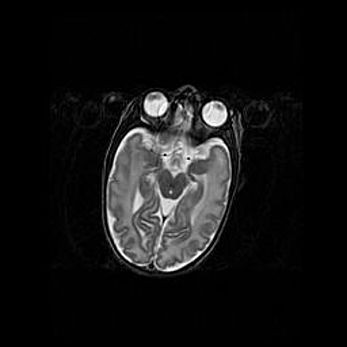

Церебральная ишемия II.

Возраст: 5 дней

Вес: 3400 г

Пол: женский

Окружность головы: 35 см

Срок гестации: 39 недель

Церебральная ишемия – это заболевание, характеризующееся недостаточностью (гипоксией) либо полным прекращением (аноксией) снабжения мозга кислородом по причине закупорки одного или нескольких сосудов. Это приводит к  что метаболическим расстройствам различной степени тяжести в тканях головного мозга, развитию коагуляционных некрозов и гибели нейронов.